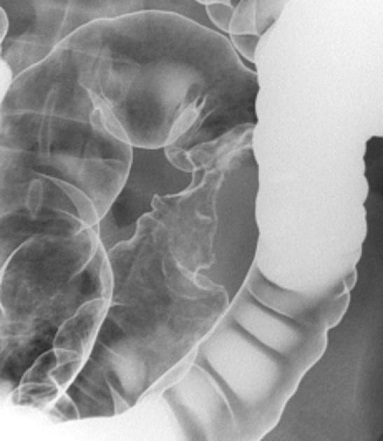

Adenocacinome du

colon ascendant , angle colique gauche . Aspect

soustraction en forme stenosant regularite

centrale d'une portion du colon droit du tumeur .

Technique de lavement baryte en double de contrast

se donne de image tres net reel de la face interne

du portion lesionelle |

Adenocarcinoma du colon droit :

Image stenosant en circonferentiel a aspect

" trognon de pomme " du colon ascendant

avec bord tres irregulierement . Lavement baryte mono de

contrast du colon transverse |